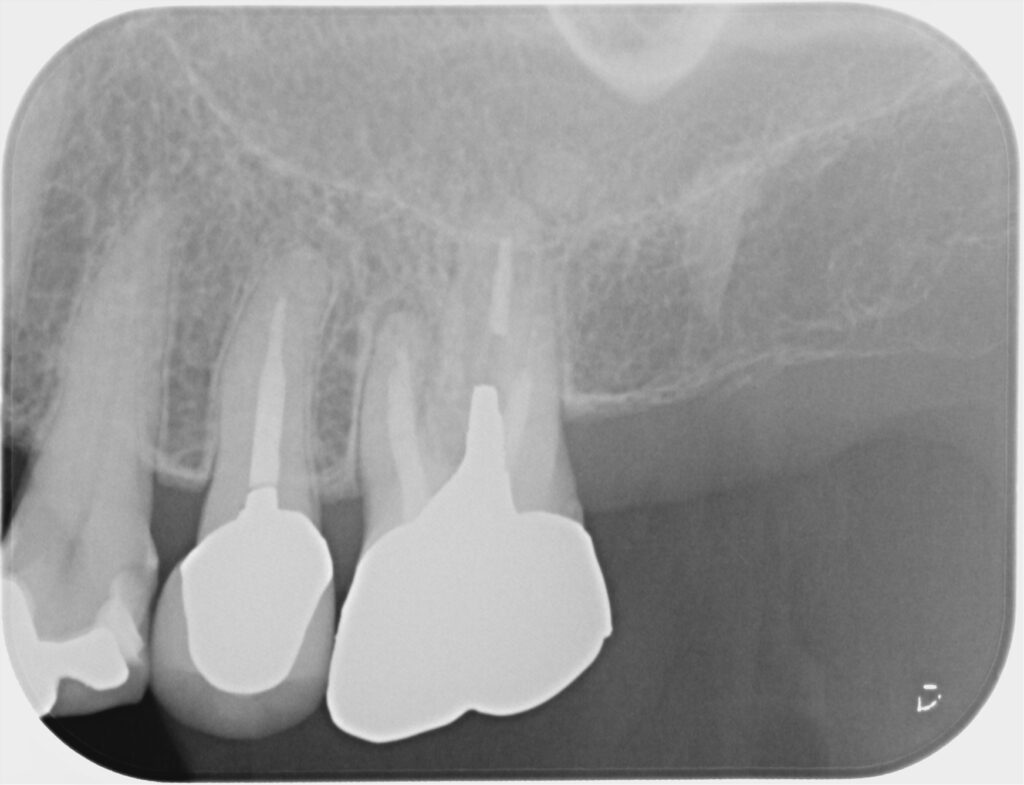

■ 初診時の状態

-

既に根管治療済み

レントゲンで根尖部に透過像

CTを撮影すると、

未処置と思われる根管の存在が疑われました。